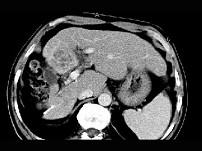

问题 女性,56岁,腹胀、双下肢水肿、乏力、食欲不振,影像所见如下图,最佳的诊断是 ( )

选项 A.酒精性肝硬化并肝血管瘤 B.血吸虫肝硬化并肝癌 C.肝炎后肝硬化并肝癌 D.局限性脂肪肝 E.原发性肝癌

答案 B